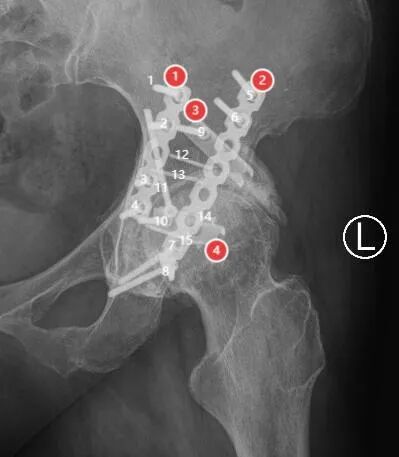

W女士,13年前因髋臼骨折行内固定手术,近2年来左髋部间断疼痛并活动受限、跛行,拟行人工髋关节置换术。

密密麻麻的钉子:

关节切口相当于内固定切口的1/3